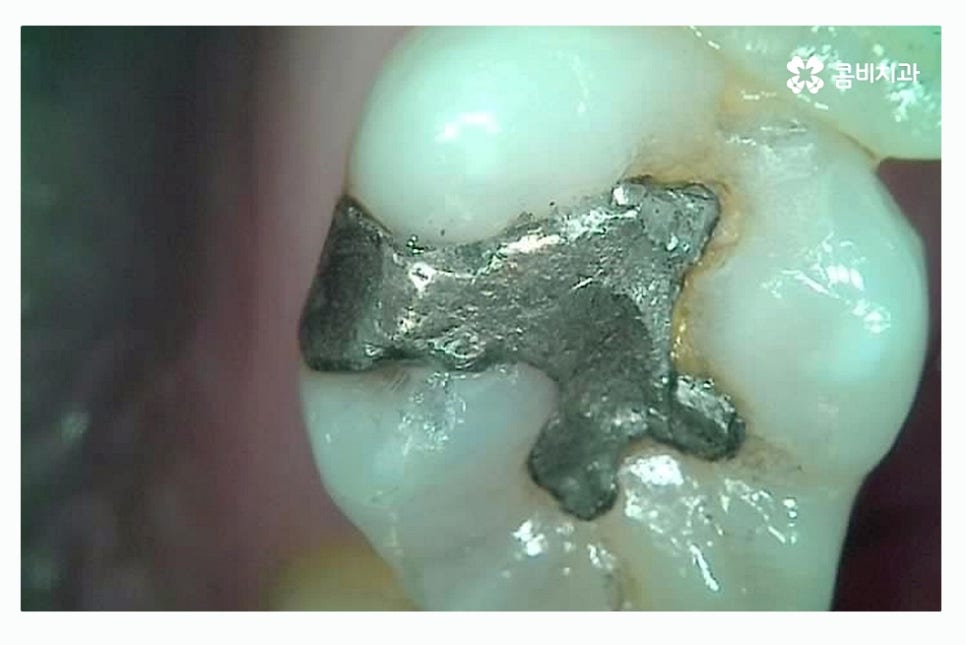

초기 충치의 경우 레진으로 간단하게 치료가 가능하지만

충치가 치아 내부로 깊어진다면 치아의 손상이 그만큼 커지기 때문에

레진으로 치료가 어려울 정도로 범위가 커진 경우에는 인레이 치료를

주로 하게 되며 인레이 치료는 세라믹, 골드 등으로 택할 수 있어요.

레진으로는 교합력이 강한 치아나 깊고 넓은 범위를 치료하는 것이 제한될 수 있기 때문에

손상된 부위를 본 떠서 인레이를 통해 치료가 필요할 수 있어요.

레진의 경우 재료가 수축는 성질이 있어 범위가 넓을 경우

미세하게 틈이 벌어지는 경우도 있기 때문에

큰 충치의 경우 인레이 혹은 크라운을 통해서

치아를 덮어 씌우게 되는데 별다른 불편함 없더라도